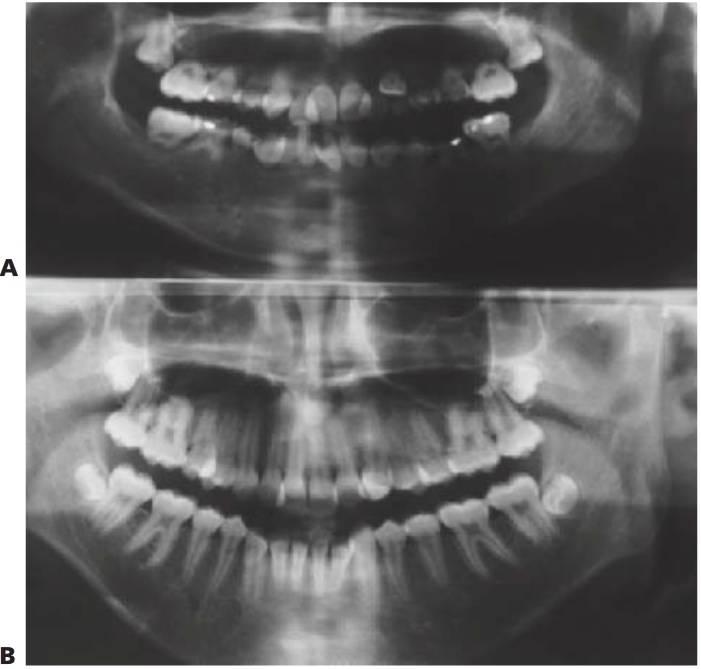

La incidencia, tanto del cáncer infantil en conjunto como de los diversos tipos, varía poco de un país a otro y ningún grupo racial se ve exento de la enfermedad. Entre más de 50 tipos de cáncer infantil, los más comunes son leucemias, linfomas, tumores del SNC, sarcomas primarios de hueso (fig. 10.7A) y tejidos blandos, tumores de Wilms, neuroblastomas y retinoblastomas. Las leucemias agudas y los tumores del SNC son responsables de en torno a la mitad de las neoplasias malignas infantiles. Los tratamientos multimodales (quimioterapia, radioterapia y cirugía) han dado lugar a una supervivencia a 5 años en casos de cáncer infantil del orden del 70%.

- Se desarrolla a partir de linfocitos B o T neoplásicos en ganglios linfáticos y tejido linforreticular (fig. 10.7B).

A excepción de aquellos niños tratados con radioterapia en la región orofacial, la mayoría no presenta mayor propensión a las enfermedades dentales y periodontales que los niños sanos, y con frecuencia mantienen una salud oral excelente. No obstante, los efectos oroden tales a largo plazo de la radioterapia influyen a veces en el tratamiento odontológico (fig. 10.9).

Osteodistrofia renal

Las lesiones líticas de la mandíbula o el maxilar superior, conocidas como tumores de Brown, se dan a veces en casos de insuficiencia renal causada por hiperparatiroidismo secundario. Histológicamente, estas lesiones son similares a los tumores de células gigantes y suelen remitir tras la corrección de la hipocalcemia y la hiperfosfatemia con metabolitos de la vitamina D. La hipocalcemia es debida a un aumento en la retención de fosfato y reducción de la absorción de caldo. La absorción activa de calcio en el intestino depende de la presencia del metabolito activo 25-hidroxi-colecalciferol (vitamina D3). Sin embargo, el metabolismo de la vitamina D se ve deteriorado por la insuficiente hidroxilación del 25-hidroxi-colecalciferol a 1,25-dihidroxi-colecalciferol en el riñón enfermo. Al intentar elevar el calcio sérico se origina un hiperparatiroidismo secundario y el calcio es obtenido de las reservas óseas, dando lugar al característico patrón radiológico de osteodistrofia renal (fig. 10.9A).